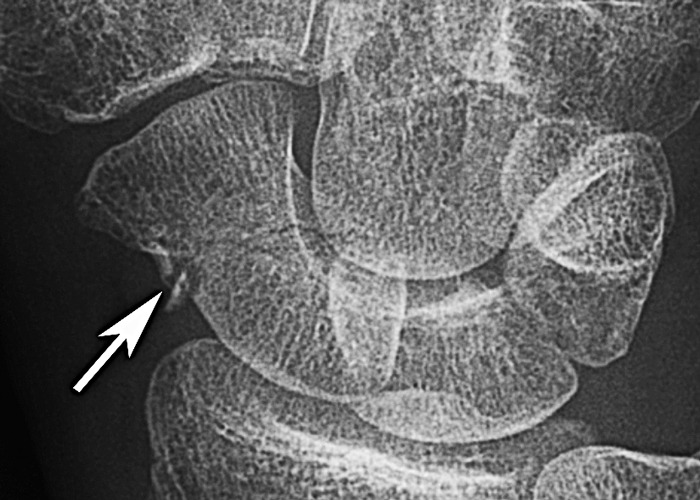

Midjefrakturer som uppvisar ett, oftast litet, avsprängt radiellt intermediärfragment är potentiellt instabila, och de har betydligt längre läkningstid och ökad risk för pseudartros även om frakturen i övrigt är odislokerad [8, 21] (Figur 4). Utöver detta bör frakturinstabilitet misstänkas om intraskafoidvinkeln är > 35 grader på lateralprojektionen [16, 22]. Om en patient med skafoideumfraktur också uppvisar en så kallad DISI (dorsal intercalated segment instability)-deformitet, vilket ses som > 60 grader vinkling mellan skafoideum och lunatum, bör man misstänka att frakturen är påtagligt instabil, alternativt att det föreligger en äldre skada i ledbandskomplexet mellan skafoideum och lunatum.

Figur 4. Exempel på komminut skafoideumfraktur med ett litet radiellt fragment. Detta frakturmönster är associerat med frakturinstabilitet och längre läkningstid, och bör föranleda vidare diagnostik med DT. Bild från Buijze 2012 [21] med tillstånd från Elsevier.